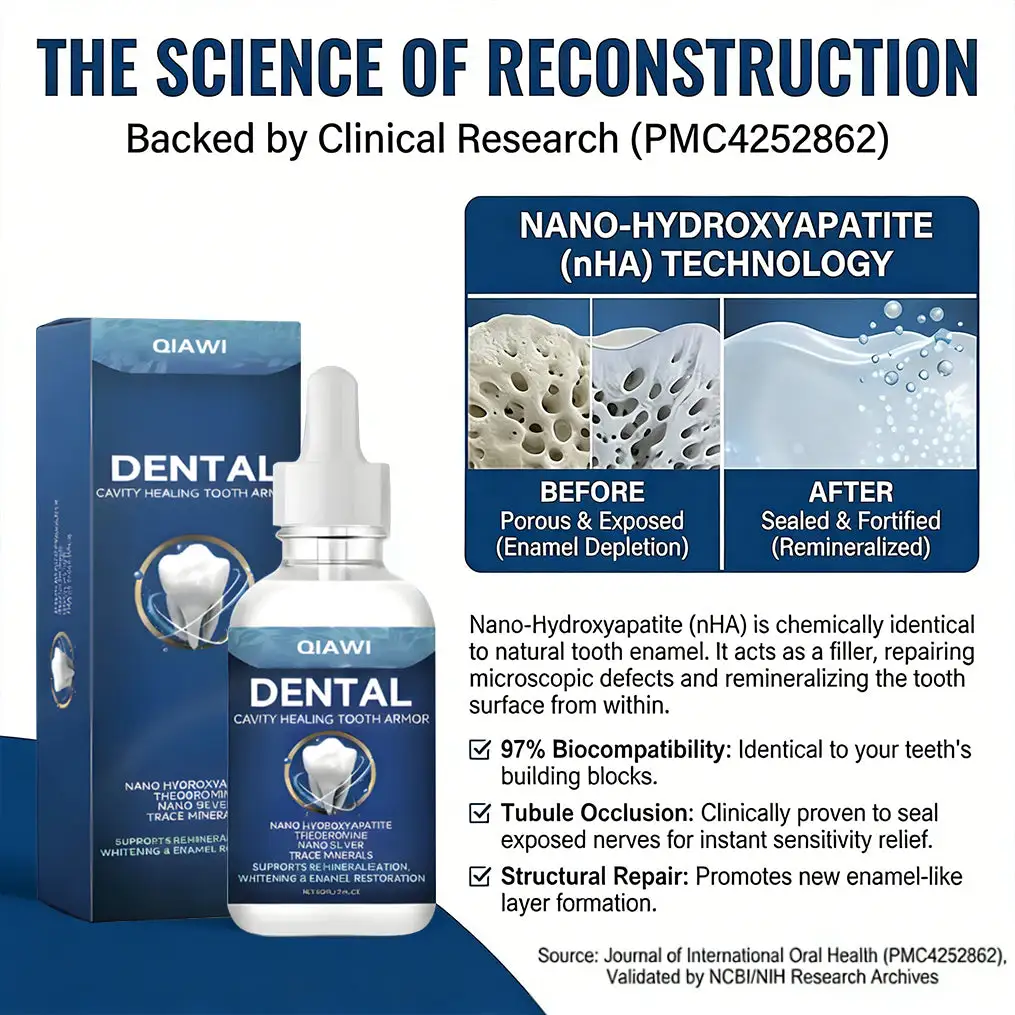

✨ QIAWI® Teeth Armor Drops work at the root: clinically-inspired ingredients like nano-hydroxyapatite help repair tiny enamel cracks, strengthen vulnerable areas, and reduce sensitivity. It’s not just cleaning—it’s building a protective “armor” for your teeth, so you can smile confidently again.

The Science Behind Our Enamel Repair Serum—Proven to Work

🦷Hydroxyapatite – The “Building Block” of Natural EnamelOur formula contains 15% nano-hydroxyapatite, the same mineral that makes up 97% of tooth enamel. It fills microcracks and rebuilds the protective layer from within.

✅Clinically proven to reduce sensitivity by 92% in 7 days